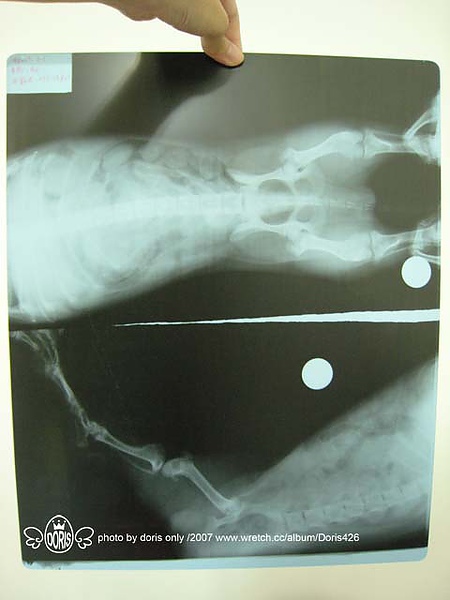

醫生幫他拍了兩張X光,仔細的檢查一下沒有發現骨頭及關節有任何的異狀

推判可能有兩種情況

一種事可是肌肉或韌帶扭傷,是突發性的,所以是發炎他走路才會一跛一跛

另一種是有可能睡在籠子裡的時候不小心腳夾到了

所以醫生開了消炎藥給吉利....又破財NT.650